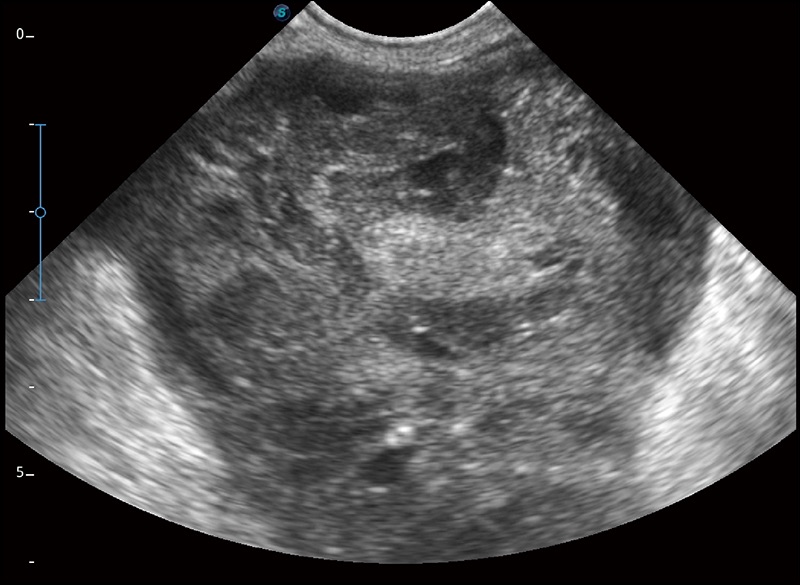

α1卓越的图像质量和便捷的工作流程,使每位宠物医生都能轻松扫查。其全面的兽用应用功能和紧凑型的结构设计,可以满足动物检查的多种需要。专业的预设检查模式和多领域测量软件包有助于为不同类型的动物提供检查, 让宠物医生能够出色的完成工作。